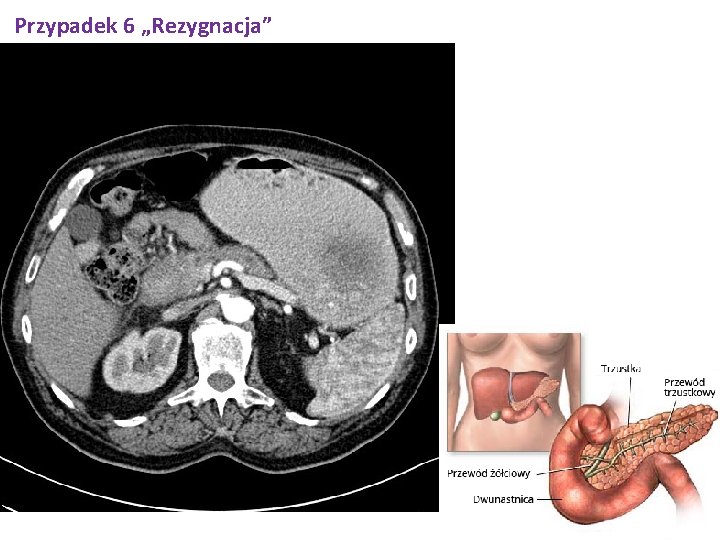

Przypadek 6 „Rezygnacja” TK jamy brzusznej z kontrastem 27. 12. 2017 Stan po alloplastyce prawego stawu biodrowego, artefakty z utwardzenia wiązki ograniczają ocenę miednicy małej. Zaleganie treści pokarmowej i podanego doustnie kontrastu w żołądku. W głowie trzustki nieostro odgraniczona, lita, hipodensyjna zmiana wlk. około 40 x 30 x 45 mm; zatarta przylegająca do zmiany okoliczna tkanka tłuszczowa, zmiana odcinkowo przylega do dwunastnicy (od strony jej okna)- prawdopodobny naciek wyżej opisanych struktur. W okolicznej tkance tłuszczowej węzły chłonne wlk. do 14 x 11 mm. Obwodowo do zmiany przewód trzustkowy poszerzony do 4 mm. Wniosek - obraz TK przemawia za guzem głowy trzustki. Wątroba niepowiększona, w obu płatach wątroby słabo odgraniczone , hipodensyjne zmiany wlk. do około 8 mm w segm VII- meta susp, ze względu na rozmiar zmian jednoznaczne różnicowanie z torbielami niemożliwe. Drogi żółciowe wewnątrzwątrobowe, PŻW nieposzerzone. Pęcherzyk żółciowy przeciętnej wielkości, cienkościenny. Obie nerki w typowym położeniu, prawa bez zmian ogniskowych, w lewej torbiel brzeżna wlk 20 mm. W miedniczce lewej nerki złóg wlk. 12 x 7 mm. UKM-y bez zastoju i prawy bez kamicy. Śledziona niepowiększona. Nadnercza typowego kształtu i wielkości, bez zmian ogniskowych. Aorta miażdżycowa. Pęcherz moczowy pusty. Zmian metastatycznych w kościach nie stwierdza się.

Przypadek 6 „Rezygnacja”